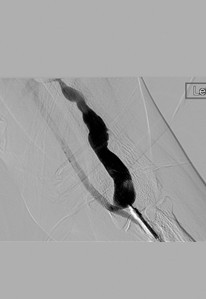

Fistulograma que demuestra la oclusión trombótica de una fístula AV braquiocefálica izquierda (nota: reflujo arterial de contraste).

Tras la primera pasada con el catéter DVX de AngioJet (no se usaron trombolíticos).